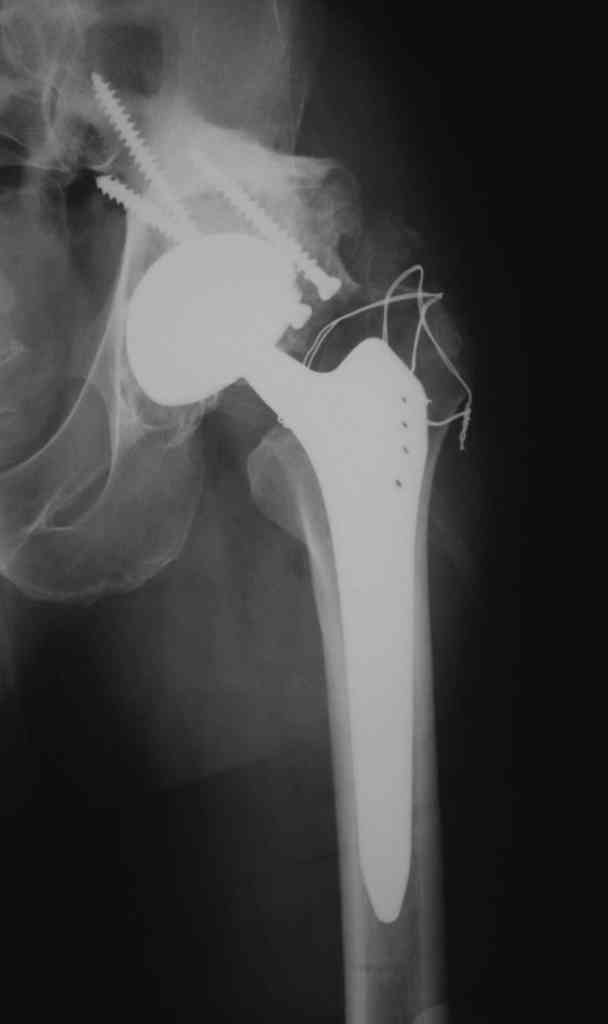

К сожалению, нередкая ситуация, мы предпочитаем выполнять операцию одномоментно - пластика задне-верхнего дефекта крыши ВВ собственной

головкой, установка вертлужного компонента бесцементной фиксации с обязательной дополнительной фиксацией винтами. Проблема будет в

восстановлении длины ноги, опыт показывает, что более 3-х см одномоментно восстановить очень сложно, и даже для этого потребуется широкая мобилизация бедра. В одном из номеров ж-ла Ортопедия травматология России мы опубликовали наш подход и р-ты лечения у больных с последствиями перелома ВВ.

Прилагаю в качестве иллюстрации одну из последних операций.

С уважением, Р.Тихилов